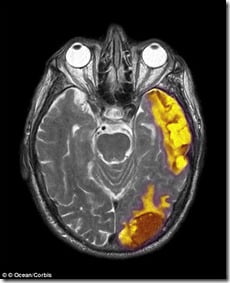

Pesquisadores descobriram áreas do cérebro responsáveis ??pelas crenças e experiências espirituais.

Há muito que se teorizou que um "ponto Deus" existe no cérebro e agora parece que não pode realmente ser mais do que um.

"Nós encontramos uma base neuropsicológica para a espiritualidade, mas não está isolado em uma área específica do cérebro", disse o professor de psicologia Johnstone.

"Algumas partes do cérebro desempenham mais funções predominantes, mas todas trabalham juntas para facilitar as experiências dos indivíduos espirituais".

Os pesquisadores da Universidade de Missouri chegaram a conclusão que a espiritualidade é um fenômeno complexo e que várias áreas do cérebro são responsáveis ??por muitos aspectos de experiências espirituais.